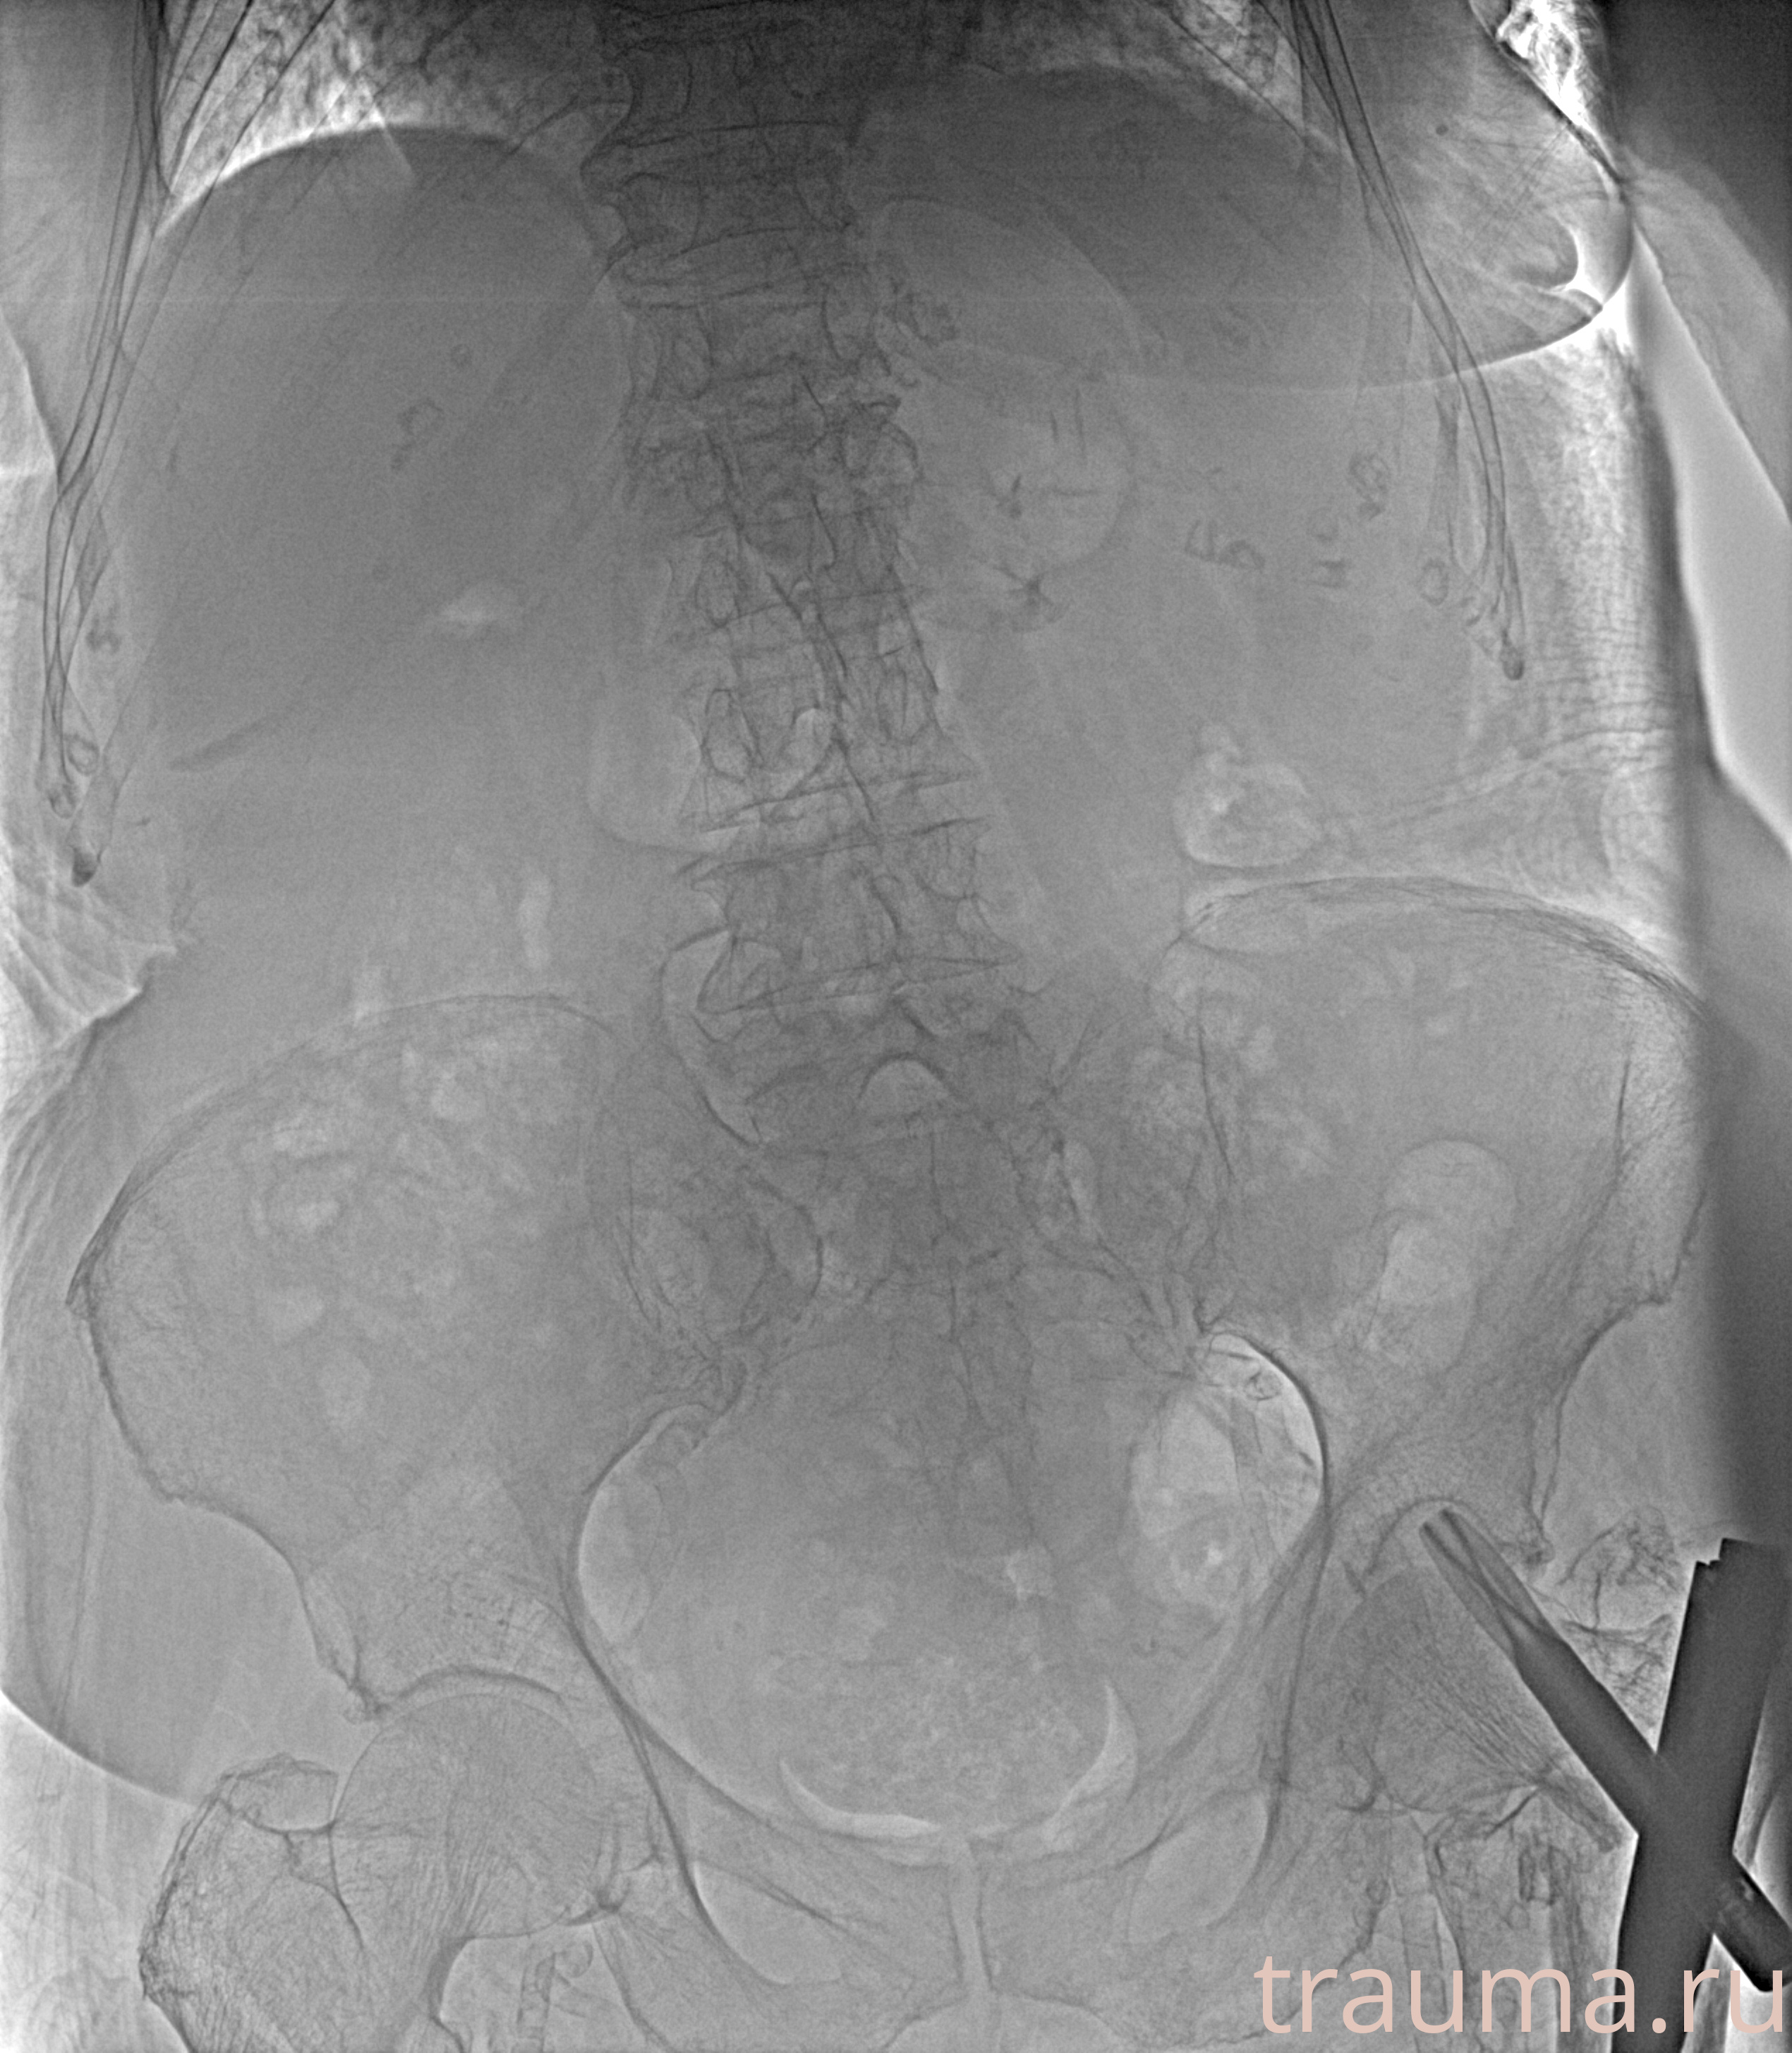

Рентген на дому: по вашему адресу приезжает врач-рентгенолог, травматолог-ортопед с мобильным рентгеновским аппаратом, проводит диагностику травмы или заболевания, делает необходимые рентгенограммы, дает рекомендации по дальнейшему лечению. Получить качественные снимки в домашних условиях возможно благодаря уникальной методике, разработанной МосРентген Центром для института  Склифосовского